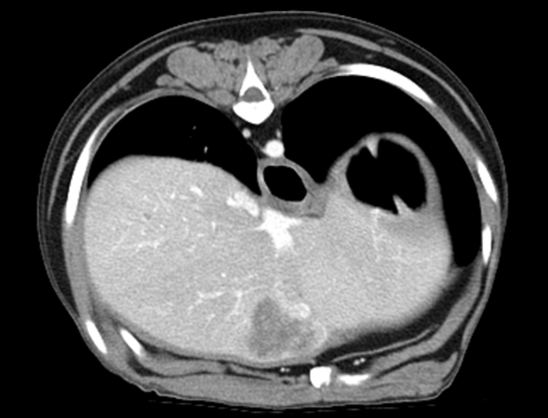

160ch CT

160 slice CT는 빠른 속도로 환자의 마취 시간을 줄이며(5분 이내) 정확한 진단에 도움을 줍니다. 또한 심장 등의 장기를 평가함에 있어 기존 64채널 CT에 비해

우수한 해상도의 영상을 획득 가능합니다.

160 slice CT는 국내 동물병원에서 최상급 촬영장비(Toshiba Acquilion Prime)에 해당하며 conventional CT 촬영 이외에도 추가적인 body perfusion,

dual energy 등도 가능합니다.

160채널 CT는 고화질 영상으로 숨어있는 비정상적인 문제점들을 찾아내어 진단 및 치료에 도움을 주고 있습니다.

02흉부 CT

· 심장의 종양 및 혈관기형(PDA 등) 평가

· 폐의 실질 변화 및 종양, 전이 평가

· 종격동 및 기관지, 식도 평가